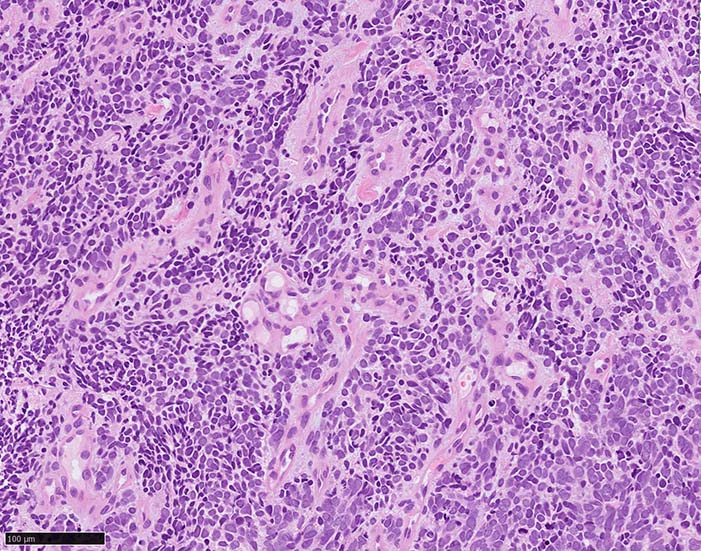

典型的な腫瘍細胞は円形, 卵円形の比較的均一な形態で「salt-and-pepper」と称される微細顆粒状クロマチンを有する小型円形核をもつ. MCPyV陽性例が均一な小型円形核を呈する傾向があり, 陰性例では, 核多形性が目立つととする報告がある.

- small cell typeは濃いクロマチン, 多形性を示す核をもつN/C比大の小型腫瘍細胞がびまん性に増殖する.

HEx40

HEx400

CK(AE1/3); CK20は含まない, のほうがdot-likeな染まりをしている. CK20は膜にも陽性になっている. LCAは陰性. 神経内分泌マーカのchromograninA, synaptophysinは陽性.